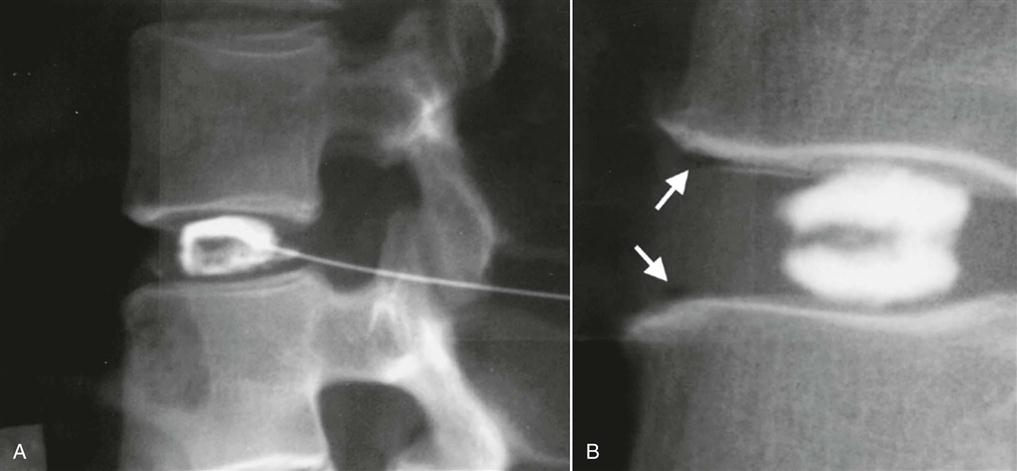

For discography, radiopaque dye is injected into the nucleus pulposus. It is not a commonly used technique but may be used to see whether injection of dye reproduces the patient's symptoms, making it diagnostic (Figure 9-125).